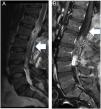

ResultsThe mean follow-up period was 27 months. No patient developed a post-operative cerebrospinal fluid (CSF) dural-cutaneous fistula. CSF leakage was not observed in the control MRIs at 6 weeks.

ConclusionsWe describe, for the first time, the use of this type of U-clip with a flat inner side. The non-penetrating titanium U-clip facilitates effective and rapid dural closure at all spinal levels due to its flat internal face when closed. The U-clips did not cause significant artefacts or distortions on the magnetic resonance imaging.